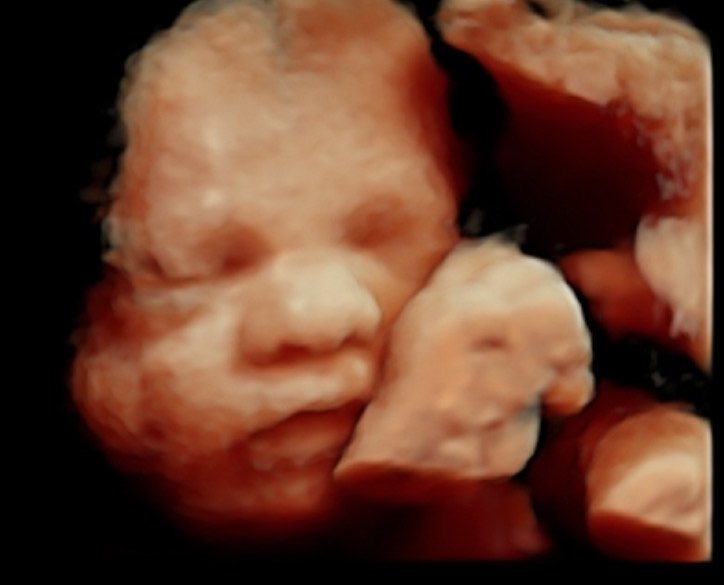

28–31 Weeks: The Perfect Window (Often the Best)

For most families, this is the optimum time. By now:

• Baby’s face is beautifully developed

• Cheeks are chubbier

• Movements are still visible

• Fluid levels are ideal

• Baby often looks more like how they’ll look at birth

Most popular window for detail and emotion.